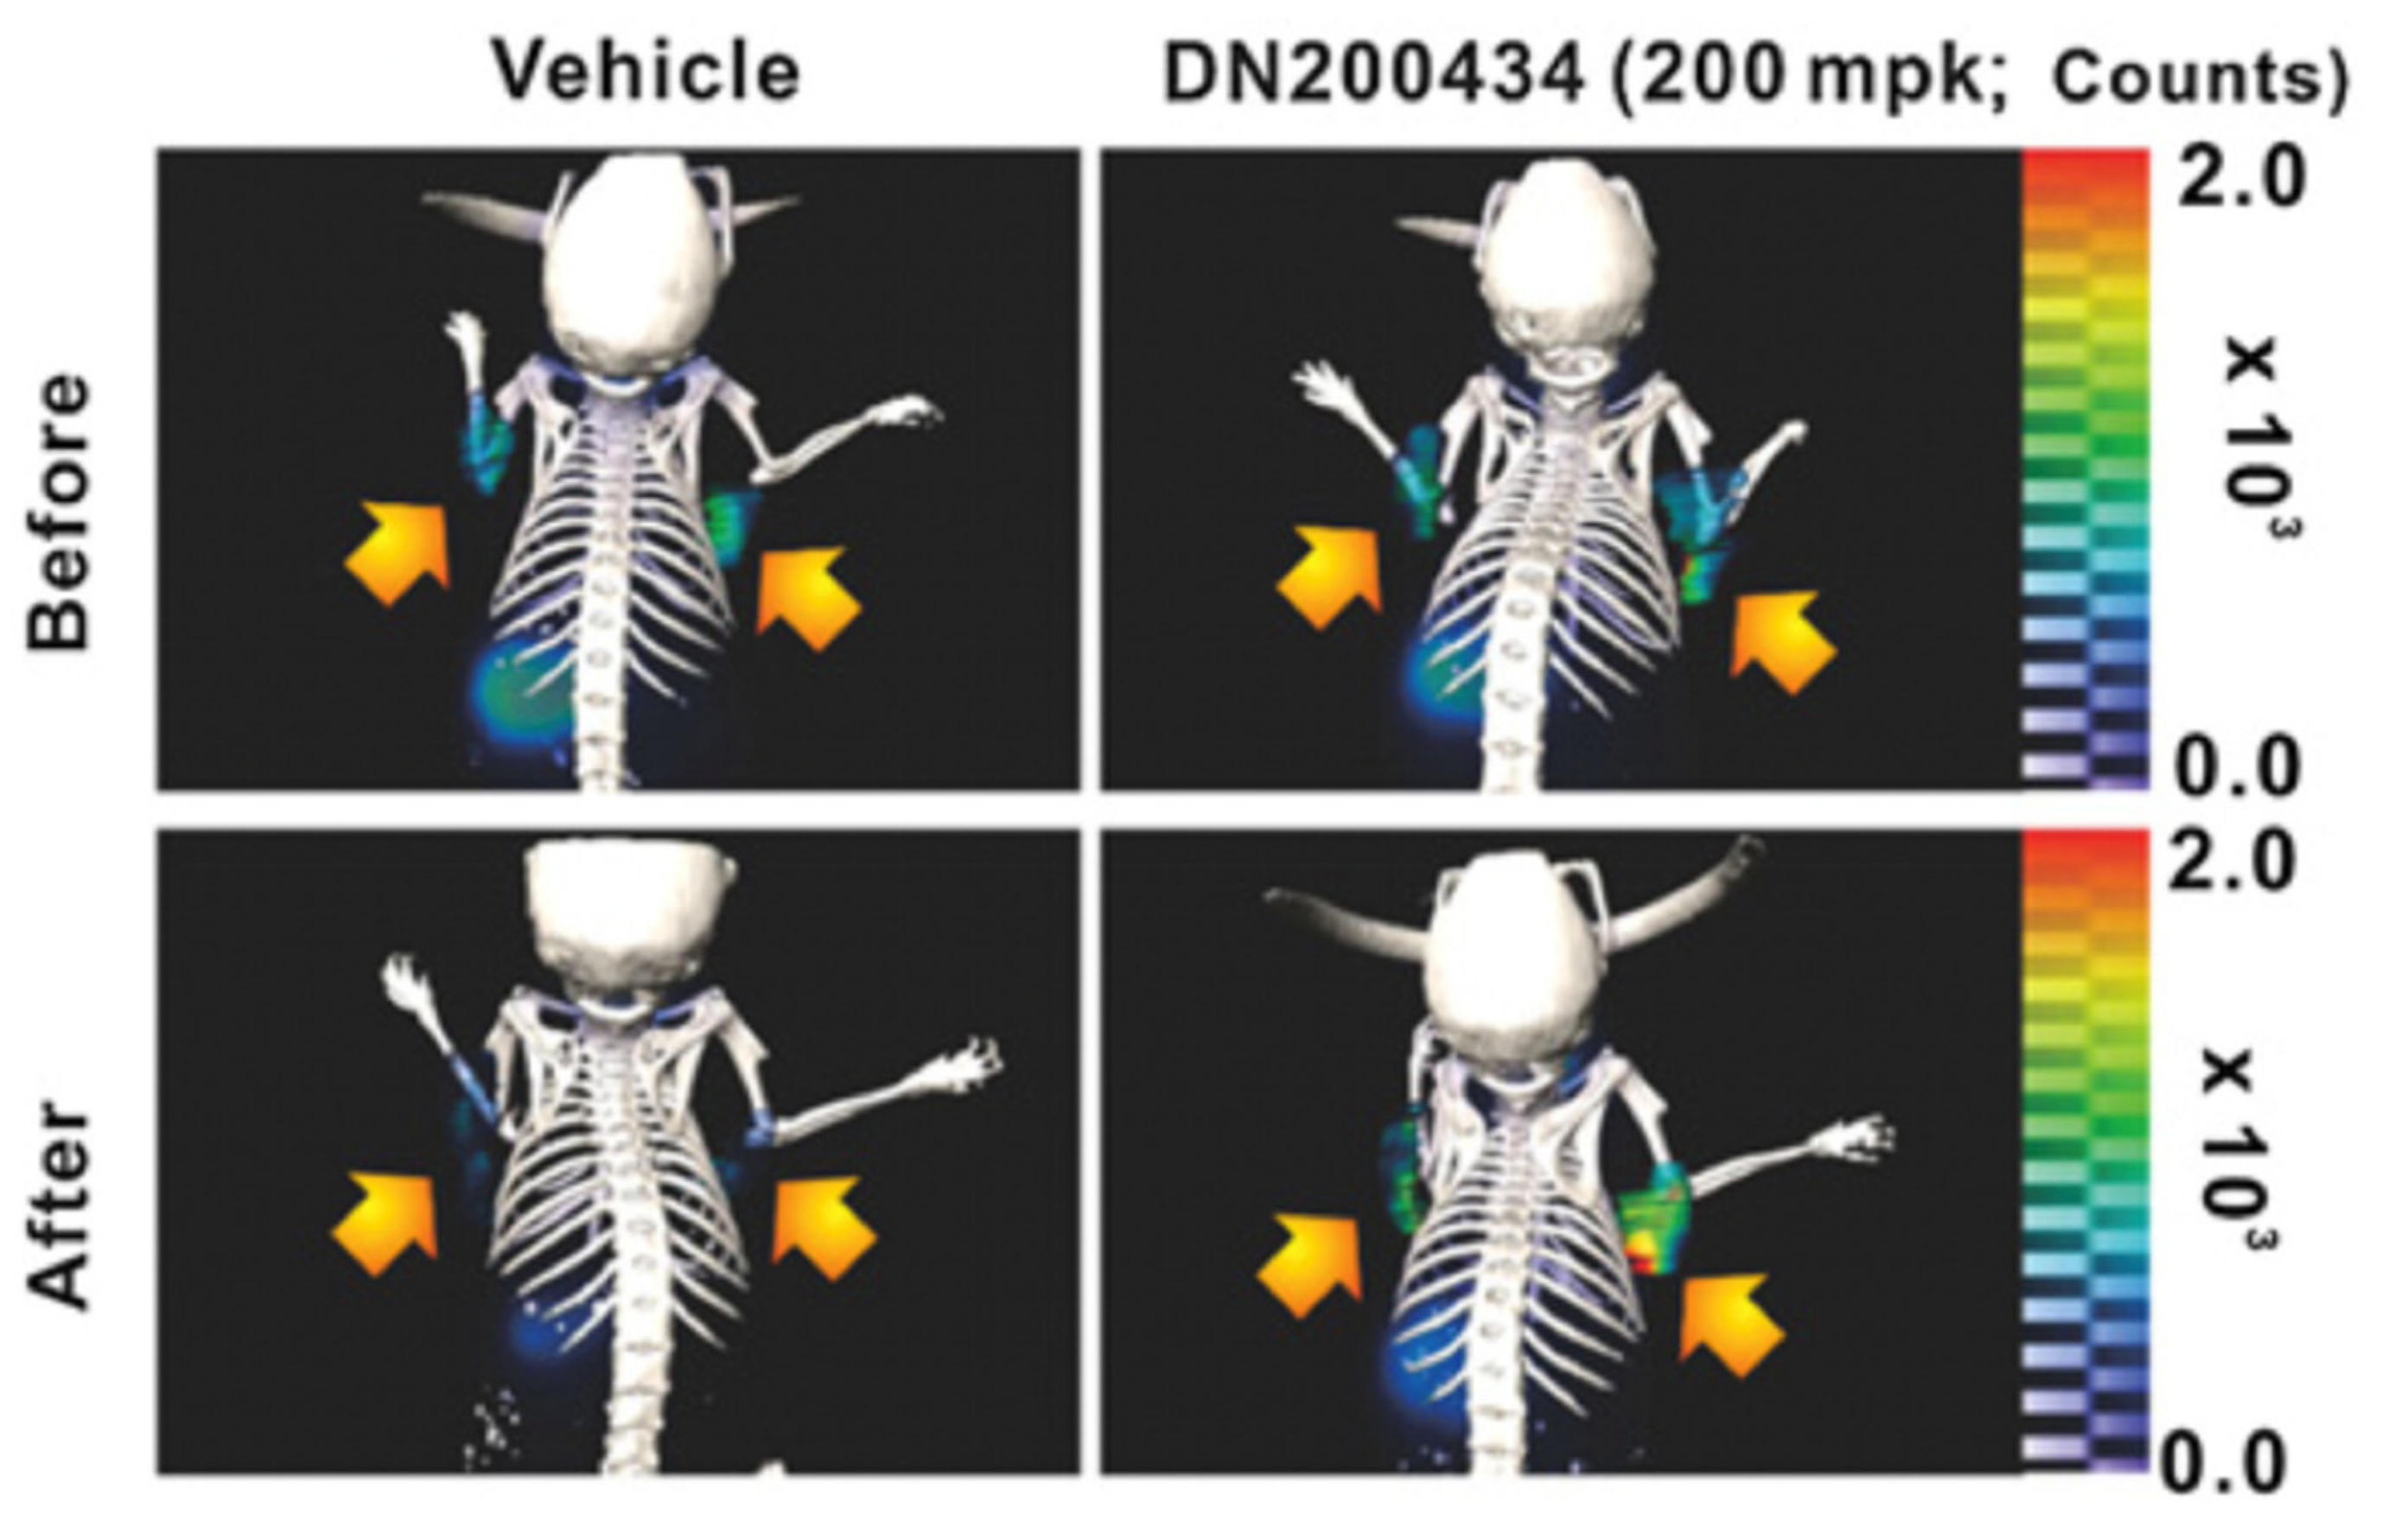

- Singh, T.D.; Song, J.; Kim, J.; Chin, J.; Ji, H.D.; Lee, J.-E.; Lee, S.B.; Yoon, H.; Yu, J.H.; Kim, S.K.; et al. A Novel Orally Active Inverse Agonist of Estrogen-Related Receptor Gamma (ERRγ), DN200434, A Booster of NIS in Anaplastic Thyroid Cancer. Clin. Cancer Res. 2019, 25, 5069–5081. [Google Scholar] [CrossRef] [Green Version]